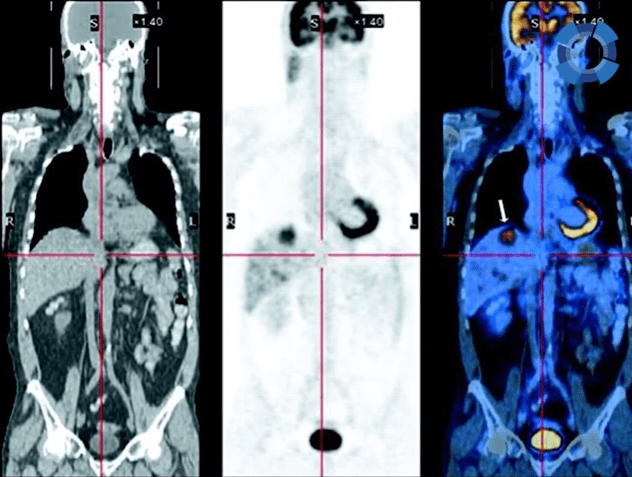

O exame de PET/CT (ou PET Scan) é um procedimento de alta qualidade que permite identificar alterações metabólicas e funcionais em todo o organismo, além de alterações anatômicas, facilitando o estudo de lesões causadas por tumores, por exemplo.

Por avaliar atividades do metabolismo, o exame é completo e capaz de detectar os tumores até mesmo antes que se manifestem anatomicamente.

Sendo assim, o exame é uma união entre os recursos da medicina nuclear com os da radiologia, o que traz uma maior resolução e qualidade para as imagens geradas nos resultados.

Cerca de uma hora após a injeção, inicia a tomografia computadorizada, que capta imagens de todo o corpo, durante 35 minutos, aproximadamente. A alta sensibilidade do PET/CT identifica sinais transmitidos pelo composto radioativo e os transforma em imagens que vão mostrar, em cor vermelha, as áreas com metabolismo intensificado, alertando o médico para alterações como um possível tumor.

A gravidade de um tumor é avaliada com base na luminosidade de algumas partes do resultado do PET/CT. Quanto mais intenso o brilho nos resultados, maior a atividade metabólica do tumor, o que é um sinal de alerta.

Então, por exemplo, se um paciente que possui câncer, já faz o tratamento com quimioterapia e realiza o PET/CT em certo momento, apresentando pouca luminosidade nos resultados, isso significa que a quimioterapia está sendo efetiva e que o organismo do paciente está respondendo bem ao tratamento.